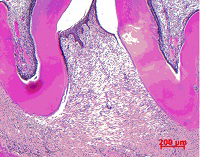

歯科治療の一例

提携 歯科技工所への発注 口腔外科疾患に対する処置

歯科口腔外科用器具による処置 歯肉処置の例

口腔外科に準じた処置 インプラントの埋入手術(上顎)